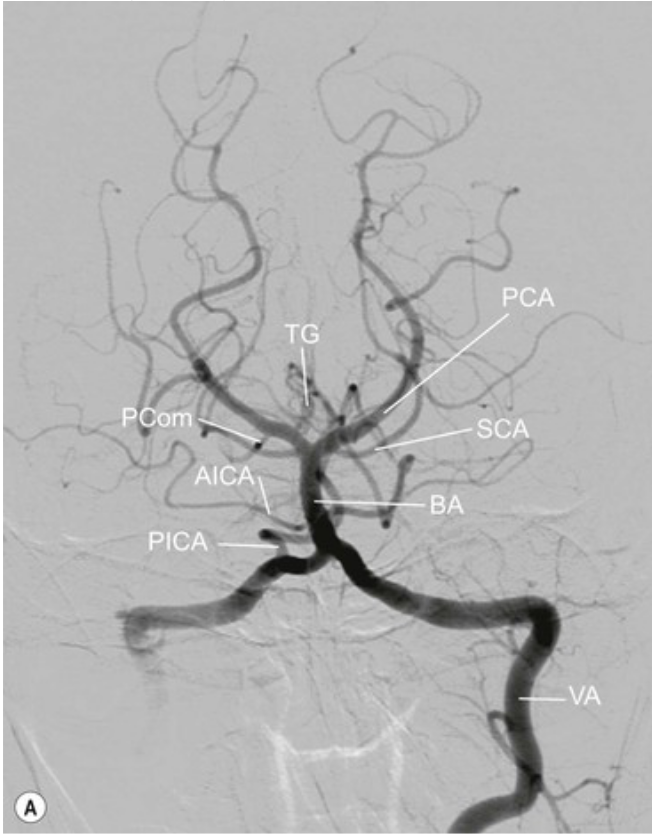

20.1 Patient presents with hemisensory loss and right homonymous hemianopia. Which vessel is affected?

PCA Contralateral